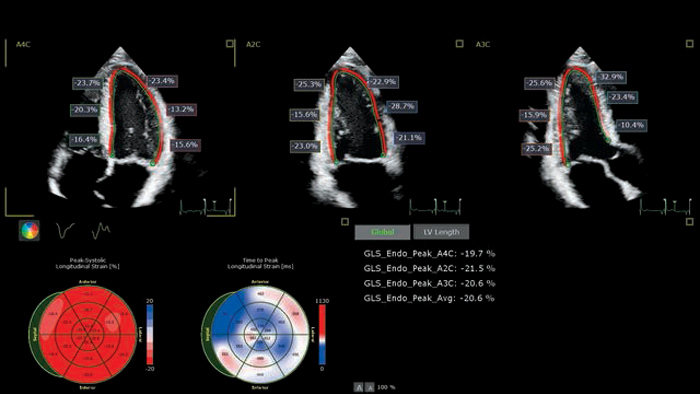

X5-1c AutoStrain

AutoSTRAIN

TOMTEC AutoSTRAIN bietet eine einfache Lösung zur Strain-Messung mit einem einzigen Knopfdruck und mittels Auto View Recognition und Auto Contour Placement mit einer Lernkurve von mehr als 6000 Bildern, um die Zuverlässigkeit zu stützen. AutoSTRAIN ermöglicht schnelle und reproduzierbare Messungen des linksventrikulären, globalen longitudinalen Strains (GLS) für die tägliche klinische Anwendung.